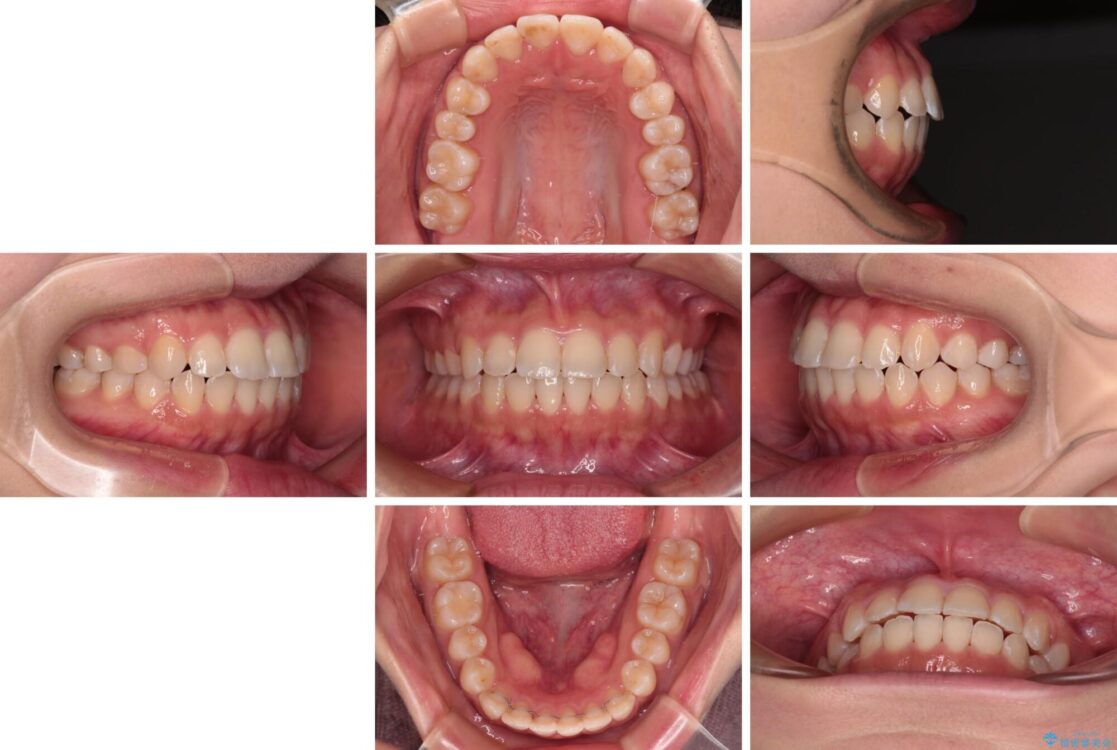

治療前

• 【モニター】短期間で終わりたい ワイヤー装置での非抜歯矯正 治療前画像